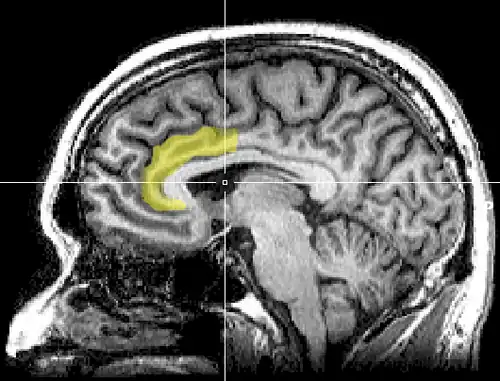

Sagittal MRI slice with highlighting indicating location of the anterior cingulate cortex.

In human brains, the anterior cingulate cortex (ACC) is the frontal part of the cingulate cortex that resembles a "collar" surrounding the frontal part of the corpus callosum. It consists of Brodmann areas 24, 32, and 33.